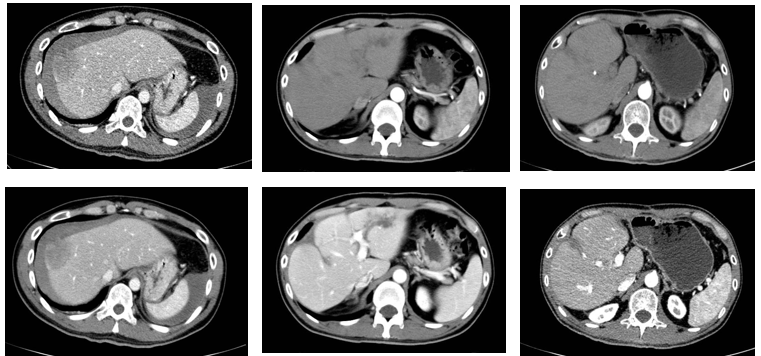

上腹部CT平扫+增强+MPR: 肝S8段见一团块状混杂异常密度影,大小约39 mm×49 mm×49 mm,病灶边界欠清,病灶密度不均匀,增强扫描病灶内见不均匀强化,动脉期明显强化,门脉期及延迟期强化稍减退,病灶部分凸出于肝脏轮廓,病灶外缘不光整,肝周及腹腔见积液密度影,肝S1见小囊状低密度影,边界清,大小约10×6mm,增强扫描未见强化。

肝S8占位,考虑肝癌破裂出血并腹腔积液

2018-10-26 急诊行介入治疗(TACE)

2018-10-30 行“剖腹探查、右肝癌切除术”,术中情况:腹腔内大量积血及血块,清除腹腔内积血和血块,探查可见右肝肿瘤、部分坏死并破裂出血,以纱布包裹;完整切除右肝肿瘤

2018-10-26 2019-5-31 2019-11-6

术前 左肝肿物切除, 复查无复发

术后病理:凝固性坏死